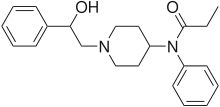

Anilidopiperidines

- 3-Allylfentanyl

- 3-Methylfentanyl

- 3-Methylthiofentanyl

- 4-Phenylfentanyl

- Alfentanil

- α-Methylacetylfentanyl

- α-Methylfentanyl

- α-Methylthiofentanyl

- Benzylfentanyl

- β-hydroxyfentanyl

- β-hydroxythiofentanyl

- β-Methylfentanyl

- Brifentanil

- Butyrfentanyl

- Carfentanil

- Fentanyl

- Lofentanil

- N-Methylcarfentanil

- Mirfentanil

- Ocfentanil

- Ohmefentanyl

- Parafluorofentanyl

- Phenaridine

- R-30490

- Remifentanil

- Sufentanil

- Thenylfentanyl

- Thiofentanyl

- Trefentanil

Structures